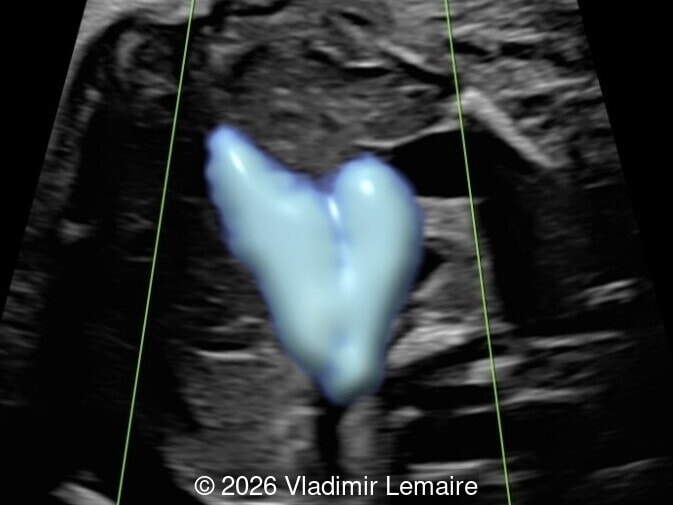

Surface mode rendering looking into the brain of the same fetus with the vein of Galen aneurysmal malformation.

Image 1 Surface mode rendering looking into the brain of the same fetus with the vein of Galen aneurysmal malformation.